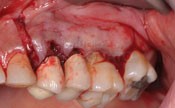

Caso clinico di Cisti Dentigena o Follicolare

Immagine radiografica iniziale

Immagine radiografica dopo l’intrvento

Immagine radiografica a guarigione avvenuta